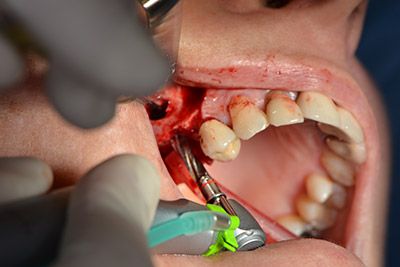

Quindi, abbiamo optato per il rialzo del pavimento sinusale con impianto simultaneo. Implantmed è preimpostato sulla prima posizione per quanto riguarda la fenestrazione buccale della parete del seno mascellare.

La fenestrazione è impostata su 35.000 rpm, mentre la mucosa nasale viene preparata in direzione craniale (da fig. 13 a 14).